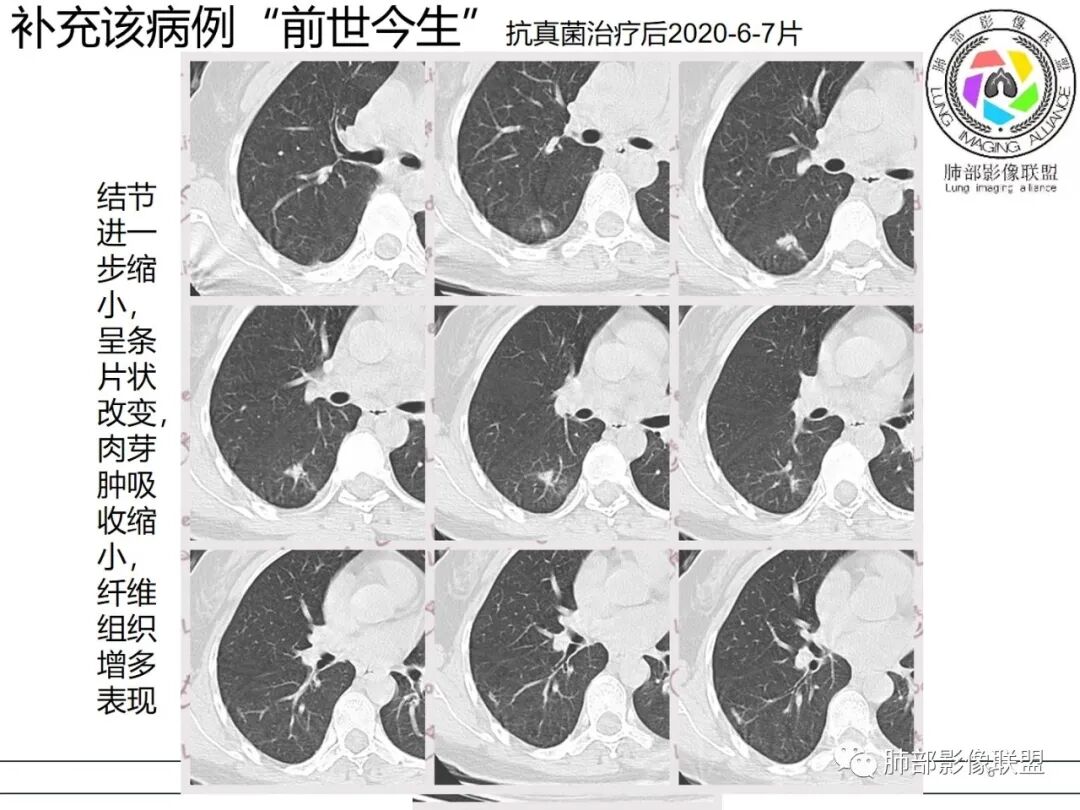

【每日晨读】前世今生---隐忍的秘密

关于结节型隐球菌

1、普通人隐球菌感染的时相:初期的隐球菌感染周围有晕,晕从多变少,或包裹,或吸收,结节实性区可迅速变大。后期(慢性期)的隐球菌周围无明显晕征,边界较清楚。

2、有些模糊晕消失慢的原因:隐球菌对周围肺组织破坏相对不重,周围所供应的营养不多,增殖也不快,呈局部相安无事的状态。隐球菌消灭之后,肺泡间隔的炎症细胞及间质恢复更慢,所以经常能见到隐球菌外面隐约带细丝的模糊影。

3、卫星灶与“蘑菇兄弟”:诊断隐球菌时,建议找卫星灶,卫星灶可以在遥远的地方。可以是遥远地方的微小结节——“小蘑菇兄弟”。有些远处的卫星灶,通常是不规则饱满实性的,晕征不明显。隐球菌的卫星灶非常“隐”,但发现率高达60%多,诊断价值高。

4、卫星灶距离远的原因:隐球菌卫星灶常很远,推测:一次空气来源隐球菌感染进入双肺多处,部分定居繁殖;距离近的隐球菌“蘑菇兄弟”常常是二次感染。

5、周围毛刺纤维、边缘形态等:坏死包裹会使得结节变圆;结节多缺乏明显的分叶征,缺乏局部突出生长能力;如果出现分叶,是由多处肉芽肿中心形成。没有坏死的局限化,结节只是凑合在一起,常呈方形征;毛刺进入晕区(概念源自南边老师),毛刺较短、较软;周围的晕吸收后,会留下不规则边,外面常残留丝状条索;收缩力较弱,临近胸膜对胸膜牵拉不明显。

6、隐球菌的毛刺消失于晕区的解释:隐球菌结节周围有间质淋巴细胞增多,肉芽肿性炎延伸,以及纤维组织增生,形态并不规则,不是因为收缩力。

7、其他:隐球菌实性区相对腺癌更实,一旦实变里面就没空气,胸膜牵拉线(小叶间隔)拉得不太紧。